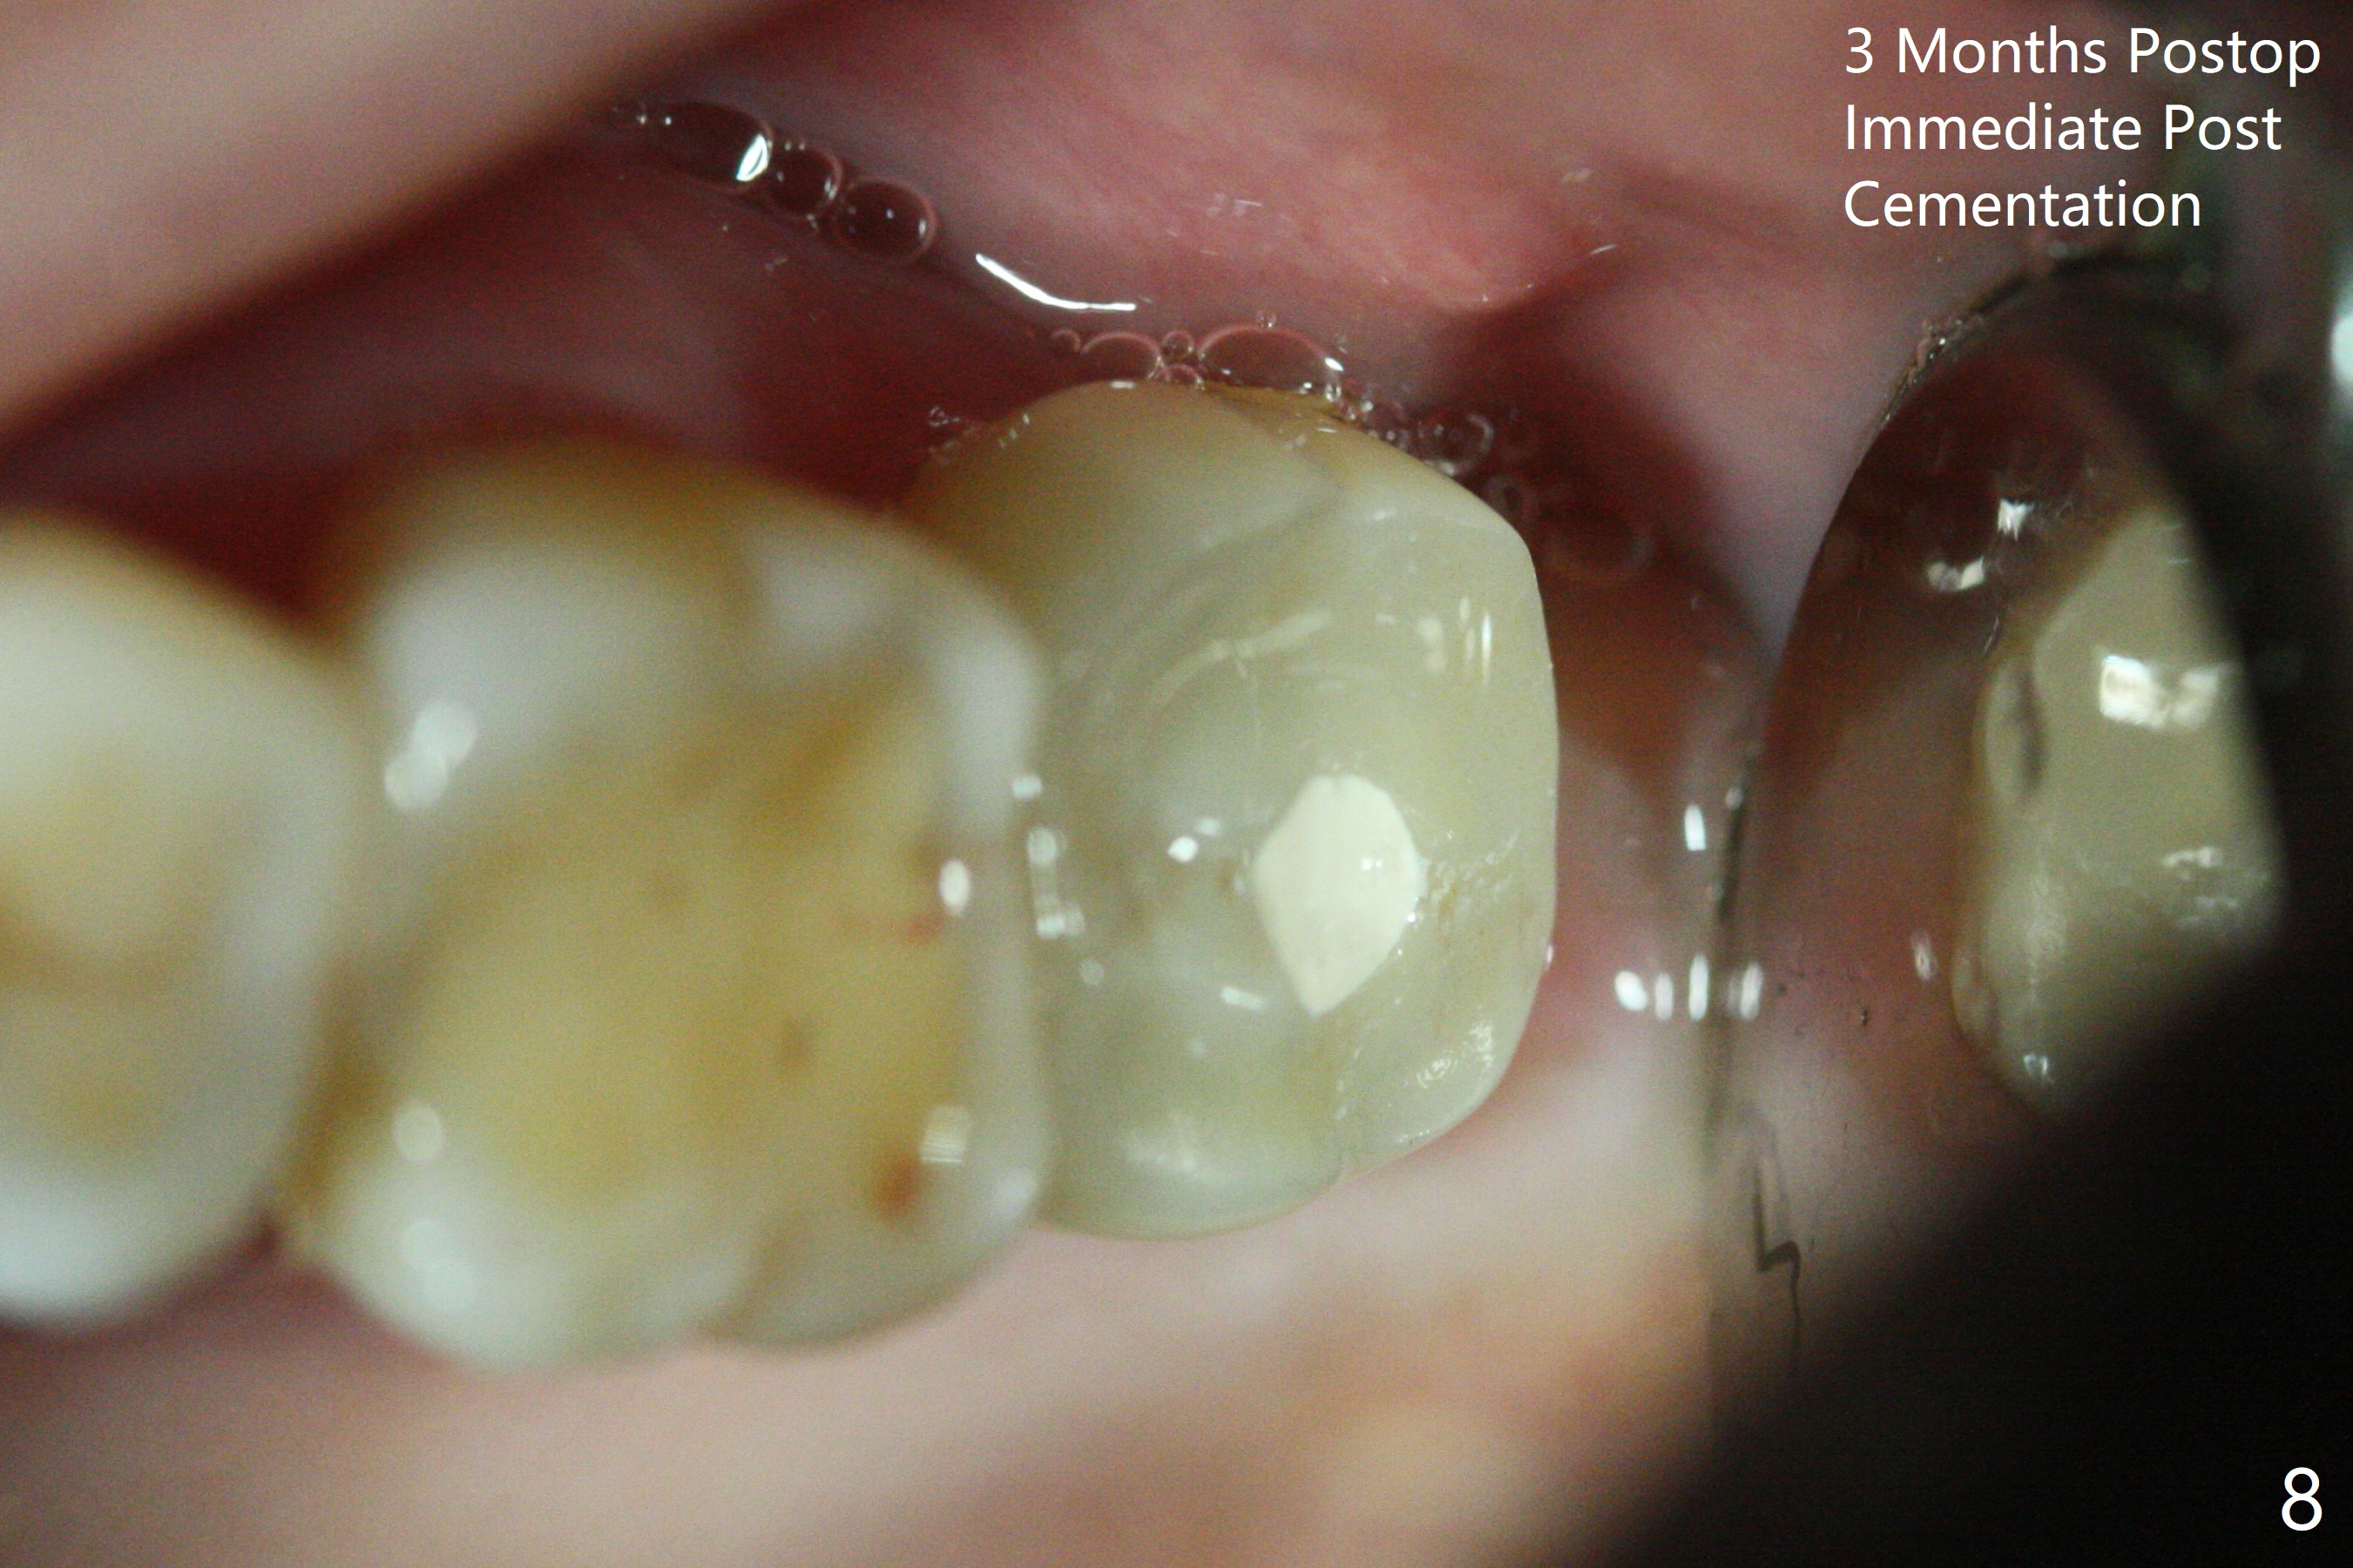

A 56-year-old woman has sign of periimplantitis 2 years 9 months post cementation. After incision, the 5.5x13 mm bone-level implant is ~ 3 mm inferior to the buccal crest. The implant is removed with 7/6 mm trephine bur, elevator and implant driver. The sinus membrane perforates. A 8x17 mm tap achieves stability (Fig.1), but the peripheral bone seems to be thin. Although a 7x14 mm tissue-level implant has stability, it is placed too deep (Fig.2). Following insertion of a piece of Osteogen plug for sinus membrane repair, a 8x14 mm implant is placed with >40 Ncm with allograft placed around the unpolished portion of the implant (Fig.3,4). A 6x3 mm abutment is placed to hold periodontal dressing in place. Because of the abutment with a slot (Fig.5 A), the periodontal dressing remains in place 4 days postop before the patient travels back home for 4 hours. In fact there is no postop sinus infection; the implant threads seems not be exposed 3 months postop (Fig.6). Because of the large implant, it is loaded early (Fig.7, 8 (Temp Bond)). Upper Molar Immediate Implant, Trajectory II 劈开术 Xin Wei, DDS, PhD, MS 1st edition 08/09/2019, last revision 04/11/2021